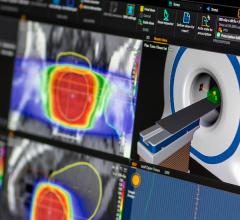

Provision, located in Knoxville, Tenn., is the latest to partner with RaySearch Laboratories on the development of its next-generation oncology information system (OIS), RayCare.

As one of the more precise methods of delivering radiation therapy for cancer treatment, proton therapy has grown at a rapid pace the last several years. Considered experimental not too long ago and used primarily in research settings, clinicians across the globe are rapidly coming to accept the utility of proton therapy for numerous indications — a list that many expect to continue to grow rapidly.

University Medical Center Groningen (UMCG) is one of the largest hospitals in the Netherlands. The hospital provides world-class patient care and is engaged in cutting-edge scientific research and medical education. UMCG is a leading cancer center and will soon open a new state-of-the-art proton therapy center.